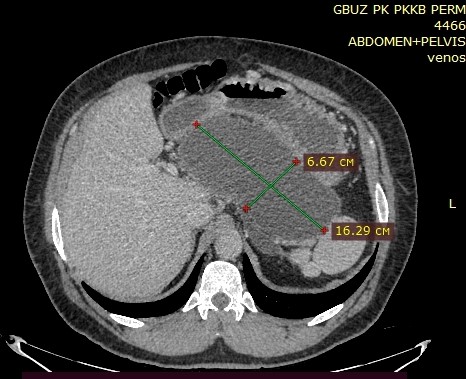

Основными жалобами при поступлении были боли в эпигастральной области и левом подреберье, подъемы температуры тела до фебрильных цифр. Почти половина пациентов (49,8 %) имели тяжелые сопутствующие заболевания. Индекс Чарльстона колебался от 0 до 9 (медиана 3). При объективном осмотре иногда (5,5 %) отмечали асимметрию живота и пальпаторно определяли образование в эпигастральной области и/или левом подреберье. Повышение в 1,5–20 раз уровня амилазы крови отмечено у 15 пациентов. По результатам УЗИ и КТ были обнаружены кисты головки и тела ПЖ у 6 человек. У остальных 30 кисты локализовались в теле и/или хвосте ПЖ. Во всех случаях диаметр кист превышал 5 см и колебался от 6 до 20,8 см (медиана 12 см). Расширение главного панкреатического протока от 4 до 11 мм диагностировали у половины пациентов (медиана 5,5 мм), гепатикохоледоха – от 8 до 12 мм – у 6 (16,67 %). Камни в желчном пузыре обнаружены у 14 больных. Во всех случаях уровень онкомаркеров был в пределах нормы. Показаниями к выполнению трансмурального эндоскопического дренирования, как и другие хирурги, считали наличие болевого синдрома, признаков инфицирования жидкостных скоплений, нарушение эвакуации из желудка или 12-перстной кишки, а также увеличение размеров жидкостного скопления [2–5]. Необходимым условием для выполнения процедуры считали наличие капсулы, толщина которой варьировалась от 1 до 6 мм.

Рис. 2. КТ органов брюшной полости с болюсным усилением, артериальная фаза. В сальниковой сумке обнаружена постнекротическая псевдокиста ПЖ размерами 6,67´16,29 см с наличием капсулы, плотно прилегающая к задней стенке ПЖ